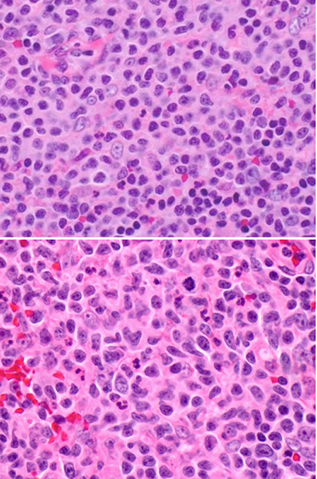

Paracortical hyperplasia, paracortex with moth-eaten appearance and has lots of lymphs which can be small to large sized, as well as immunoblasts, histiocytes and plasma cells

Late: prominent paracortical hyperplasia with numerous scattered immunoblasts and hypervascularity

Micro:

- expanded paracortical area

- sheets and clusters of immunoblasts may mimic DLBCL

-- these immunoblasts are CD30+, CD15-, ALK1 neg, EMA neg, CD45+ and EBV+, and some are T-cells (PAX5+) and some are T-cells (CD3+)